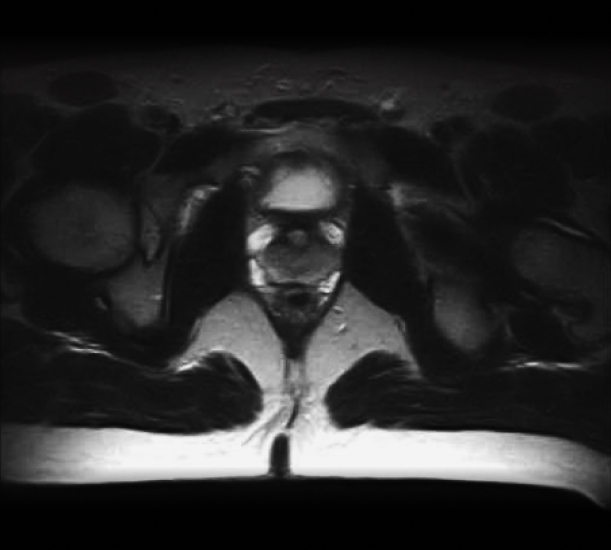

Оптимальна сила магнітного поля, 0,5 Тесла

Проблеми, викликані фізикой магнітних полей ERE та ESE

Можливості в інтервенційній та діагностичній імагінгі при використанні МРТ з високою продуктивністю та низькою силою поля

НАЙВИЩА ЯКІСТЬ ЗОБРАЖЕННЯ МРТ В РЕАЛЬНОМУ ЧАСІ ПІД ЧАС ОПРОМІНЕННЯ

AURORA RT 0.5 T MRI

Відсутність ERE та ESE виключає необхідність спеціалізованого МРТ TPS

4. "Немає" ефекту повернення або потоку електронів (ERE, ESE)

5. Оптимальна сила магнітного поля